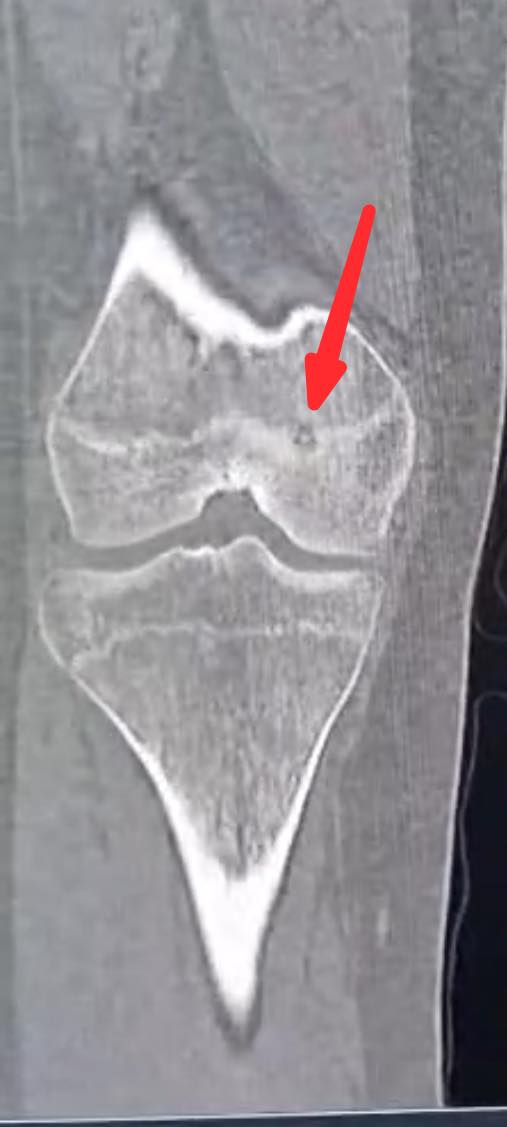

اجرى الكادر الطبي في مستشفى الأميرة بسمة عملية نوعية دقيقة لعلاج ورم عظمي حميد من نوع (Osteoid Osteoma) باستخدام تقنية الكي بالتردد الحراري (Radiofrequency Ablation) الموجهة بالأشعة المقطعية.

وبين الفريق الطبي أن خصوصية هذه الحالة تكمن في عمر المريضة (14 عاماً) حيث استقر الورم مباشرة على صفيحة النمو (Growth Plate) في عظم الفخذ البعيد. وتعتبر هذه المنطقة من الحساسية بمكان إذ ان أي خطأ قد يؤثر على النمو المستقبلي للعظم ما جعل استخدام تقنية الكي الحراري تحديا كبيرا يتطلب دقة فائقة لتجنب إلحاق أي ضرر حراري بالأنسجة المحيطة.